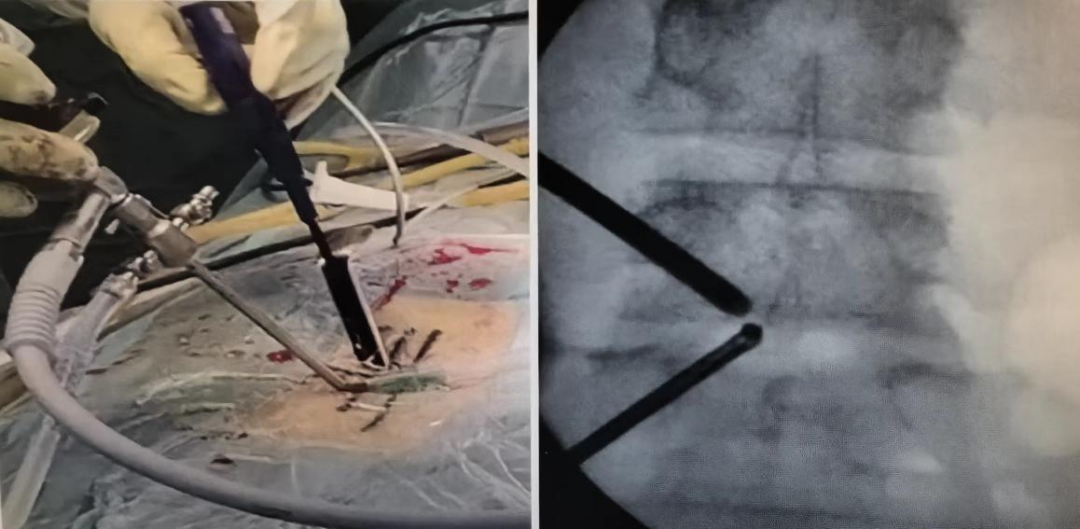

术中操作

UBE技术是什么手术

UBE(Unilateral Biportal Endoscopy)技术是指单侧双通道内镜下的脊柱手术,是一项脊柱微创可视手术,适用于颈椎、胸椎和腰椎的退行性病变。UBE技术属于微创手术方法,通过两个小切口,建立一个观察通道和一个工作通道,从而实现对病变组织的精准定位和切除。相比传统的脊柱手术,UBE技术具有创伤小、恢复快、并发症少等诸多优势。

在充分完善术前准备,与患者及家属细致沟通后,制定适合患者的个性化手术治疗方案——采用精准、创伤小、疗效好、安全、并发症少等优点的UBE下单侧入路双侧椎管减压(ULBD)技术治疗。手术非常成功,术后患者的右下肢疼痛感和麻木感完全消失,第二天佩戴腰围后即可下床行走活动,她对治疗效果非常满意。